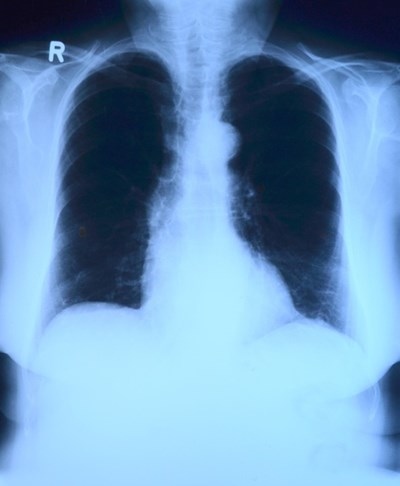

За ефективното функциониране на белите дробове е необходимо добро кръвообращение. Ако белите дробове страдат от недостиг на кислород, това е сигурен знак, че имате проблем със сърцето. Ако внезапно усещате затруднено дишане, трябва да се консултирате с Вашия лекар.